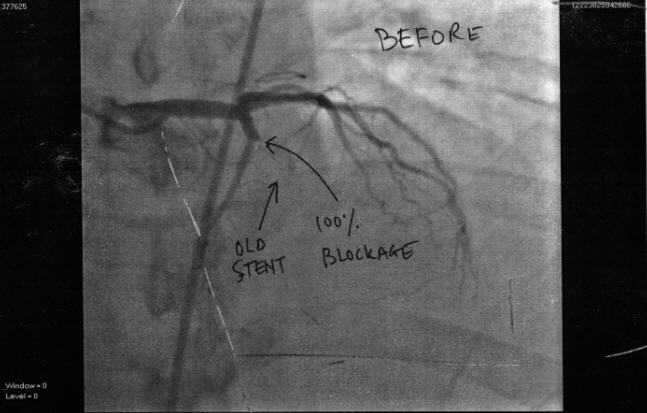

7 years ago I had a heart attack and a stent put in. Wednesday I had another heart attack due to that stent becoming completely blocked. I arrived home from hospital about 2 hours ago. I will try and get some scans made of the pictures tomorrow.